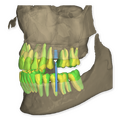

It is our most comprehensive planning option, and includes all the 3D treatment simulations needed for each case, such as ortho, perio, implants, grafts and orthognathic surgery.

Our 3D simulations showcase various treatment suggestions, facilitating a deeper understanding of the required procedures. This leads to the creation of a broader treatment plan and enables a more efficient communication with your patients.